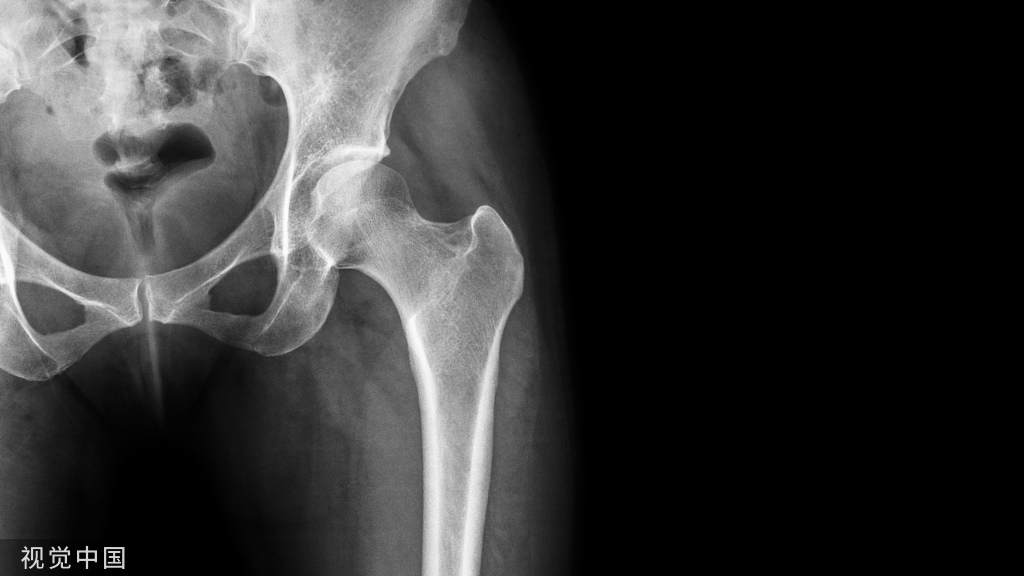

X线检查X片可见肌腱及其腱鞘有钙质沉积。也有助于本病的诊断。

桡骨茎突狭窄性腱鞘炎 X线片